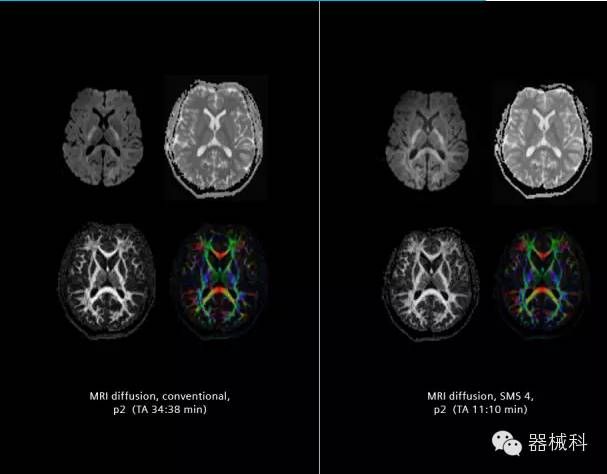

在2015年RSNA上,西門子隆重發(fā)布了Simultaneous Multi-slices 技術(即同時多層采集技術,簡稱SMS),這是磁共振掃描技術中第一次引入“同時多層”的概念,此概念技術的發(fā)布,將對未來磁共振成像領域帶來巨大的變革!

擁有了SMS“同時多層”采集技術之后,用戶可以在非常短的時間內(nèi)完成MR掃描,結合西門子靜音技術,大大提高患者的舒適性,或在單位時間內(nèi)采集更多的數(shù)據(jù),也可以得到高精度、高準確性、大數(shù)量的功能成像數(shù)據(jù),為臨床和科研提供強大的支持。專家認為,SMS“同時多層”采集技術未來在 提高成像質(zhì)量、外科手術計劃、降低術后神經(jīng)功能缺陷、提高fMRI的時間采集效率、提高靜息態(tài)功能磁共振數(shù)據(jù)質(zhì)量等方面將帶來深遠影響,希望該技術可以盡早面世,引領磁共振進入多層時代!